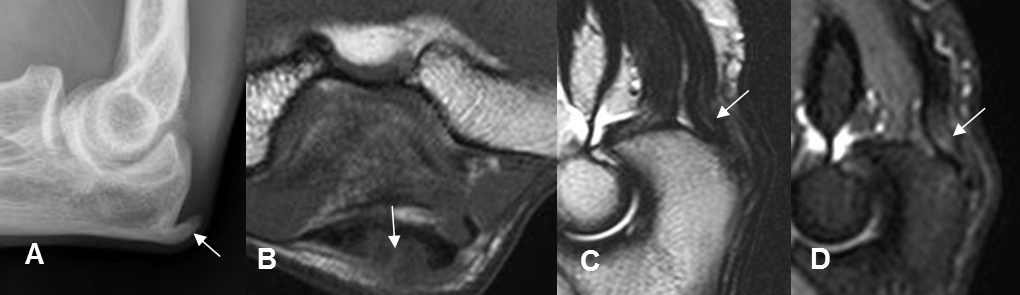

Fig 53 B. Tendinitis triceps.

A: Rxlateral. Calcificación sobre la inserción del tendón del triceps, por tendinitis crónica.

B: RM axial, C: RM sagital en T2 y D: RM sagital en STIR. Fibras del tendín del triceps hipointensas en T1, hiperintensas en T2 y STIR, por tendinitis.